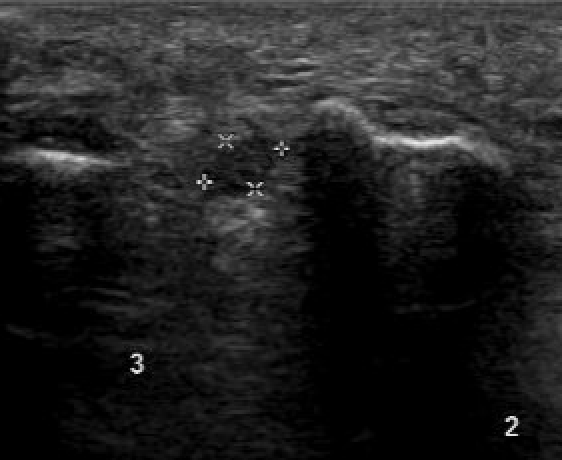

Ultrasound

mortonsMortons

Bignotti et al Eur J Radiol 2015

- systematic review of US versus MRI for Mortons

- equal accuracy